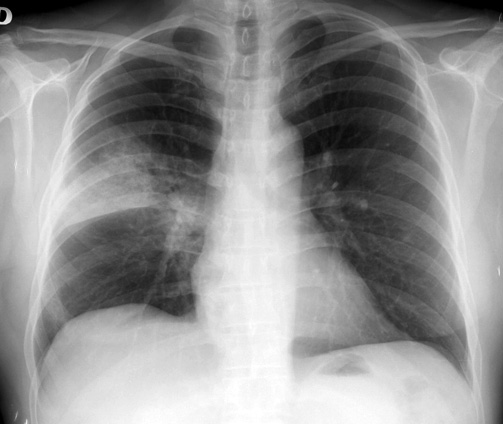

Neumonía adquirida en la comunidad: actualización

Boletín INFAC, Información farmacoterapéutica de la Comarca, vol 24 nº 5, 2016